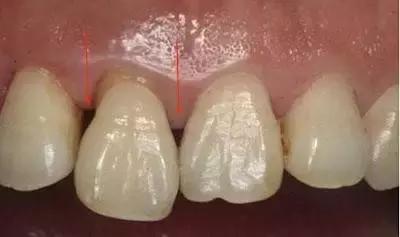

正常情况下,我们的牙齿相互接触,牙齿间会留下很小的缝隙,也就是我们所说的牙缝。这个时候的牙缝非常地窄,窄到只能用牙线这类型很薄的物品才能通过。

但是,当相邻的两颗牙齿因为一些不正常的原因,而失去了他们彼此应有的接触关系后,牙缝就会慢慢地变宽,从而出现了“卡肉”的现象。

1/ 牙齿的接触面有蛀牙,造成了牙缝变宽。